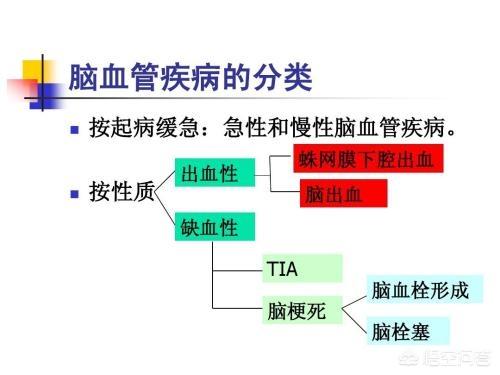

まず、脳卒中、脳梗塞、脳血管障害、この3つは同じ意味だが、人によって呼び方が違う。例えば、言葉が不明瞭になる、口が曲がる、片側の手足が弱くなる、このような症状に対して、私たち庶民の最初の反応は「脳卒中かもしれない」だが、病院では「脳卒中」または「脳血管障害」と呼ばれる。このように、前者は一般的な呼び名であり、後者は医学用語である。

その分類をよりよく理解するために、以下の図にまとめた:

脳梗塞は、以前は脳梗塞とも呼ばれ、患者さんやご家族の負担が非常に大きい、脳の虚血性疾患の一つです。脳梗塞以外にも一過性脳虚血発作などの脳の虚血性疾患があります。

すなわち、脳梗塞には脳血栓症が含まれるが、脳血栓症は種々の塞栓物の脱落により脳の血管が閉塞して起こるもので、その主なものに脳血栓症、ラクナ梗塞、脳塞栓症がある。このうち、脳血栓症は動脈硬化によるものが多く、脳塞栓症は心臓病による塞栓物の脱落によるものが多い。脳血栓症は脳梗塞の中で最も頻度の高い疾患であり、ハイリスク群では注意が必要である。

1、まず脳梗塞とは何かについて、脳梗塞は虚血性脳卒中(脳虚血性脳卒中)とも呼ばれ、脳の血液供給の障害、虚血、低酸素を指し、その結果、脳組織の虚血壊死や軟化が制限される。脳梗塞の一般的な臨床型は、脳血栓症、ラクナ梗塞、脳塞栓症である。